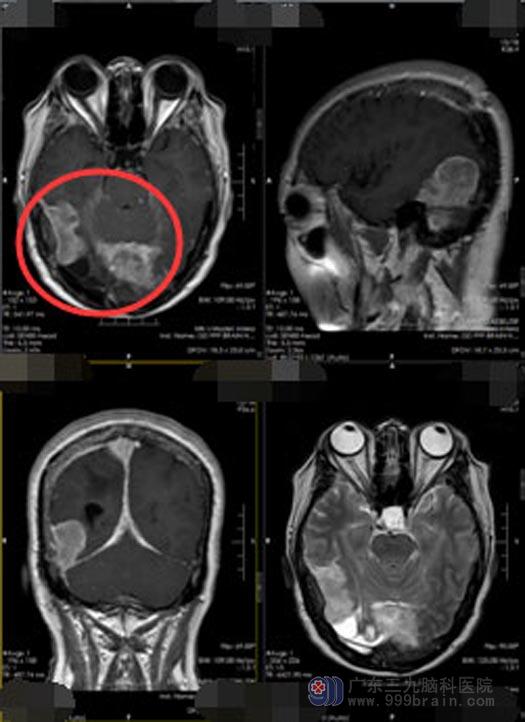

入院后,李阿姨告诉主管医生郭敏:自己的精神、胃口还好,偶有头晕头痛,右侧耳鸣,双眼看不清东西。参考李阿姨的症状、体征以及头颅MR检查,初步诊断 “右侧颞顶枕部、上矢状窦、直窦、窦汇跨小脑幕上下多发占位”,具有手术指征。

术中发现,患者的硬脑膜与骨瓣粘连严重,硬膜多处破损,予以止血悬吊硬膜后再扩大剪开硬脑膜,逐步显露顶枕部及右侧横窦小脑幕上肿瘤,顶枕叶皮层呈原术后改变,黄色囊变不成形并与脑室相通。肿瘤严重侵犯静脉窦,呈黄白色,质韧,与周围脑组织粘连紧密,逐步显露顶枕部大脑镰至肿瘤,见肿瘤广基与大脑镰相连,血供丰富,肿瘤跨镰到对侧,先电凝切开肿瘤基底,分块完成切除;再分离右侧横窦小脑幕上肿瘤并完全切除。